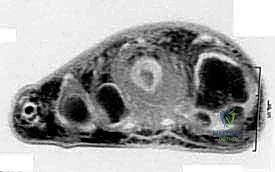

* Magnetic Resonance Imaging (MRI): This is indispensable for evaluating soft tissue involvement, intramedullary extent of bone tumors, and the relationship of the tumor to neurovascular bundles and tendons. It helps determine the precise level of amputation needed to achieve clear margins.

FIG 2 • C. MRI shows the amount of soft tissue involvement.

FIG 2 • F. MRI shows soft tissue involvement.